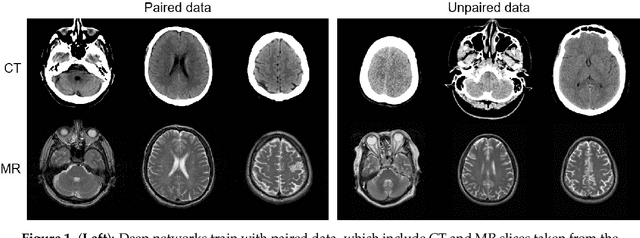

Abstract:MR imaging will play a very important role in radiotherapy treatment planning for segmentation of tumor volumes and organs. However, the use of MR-based radiotherapy is limited because of the high cost and the increased use of metal implants such as cardiac pacemakers and artificial joints in aging society. To improve the accuracy of CT-based radiotherapy planning, we propose a synthetic approach that translates a CT image into an MR image using paired and unpaired training data. In contrast to the current synthetic methods for medical images, which depend on sparse pairwise-aligned data or plentiful unpaired data, the proposed approach alleviates the rigid registration challenge of paired training and overcomes the context-misalignment problem of the unpaired training. A generative adversarial network was trained to transform 2D brain CT image slices into 2D brain MR image slices, combining adversarial loss, dual cycle-consistent loss, and voxel-wise loss. The experiments were analyzed using CT and MR images of 202 patients. Qualitative and quantitative comparisons against independent paired training and unpaired training methods demonstrate the superiority of our approach.